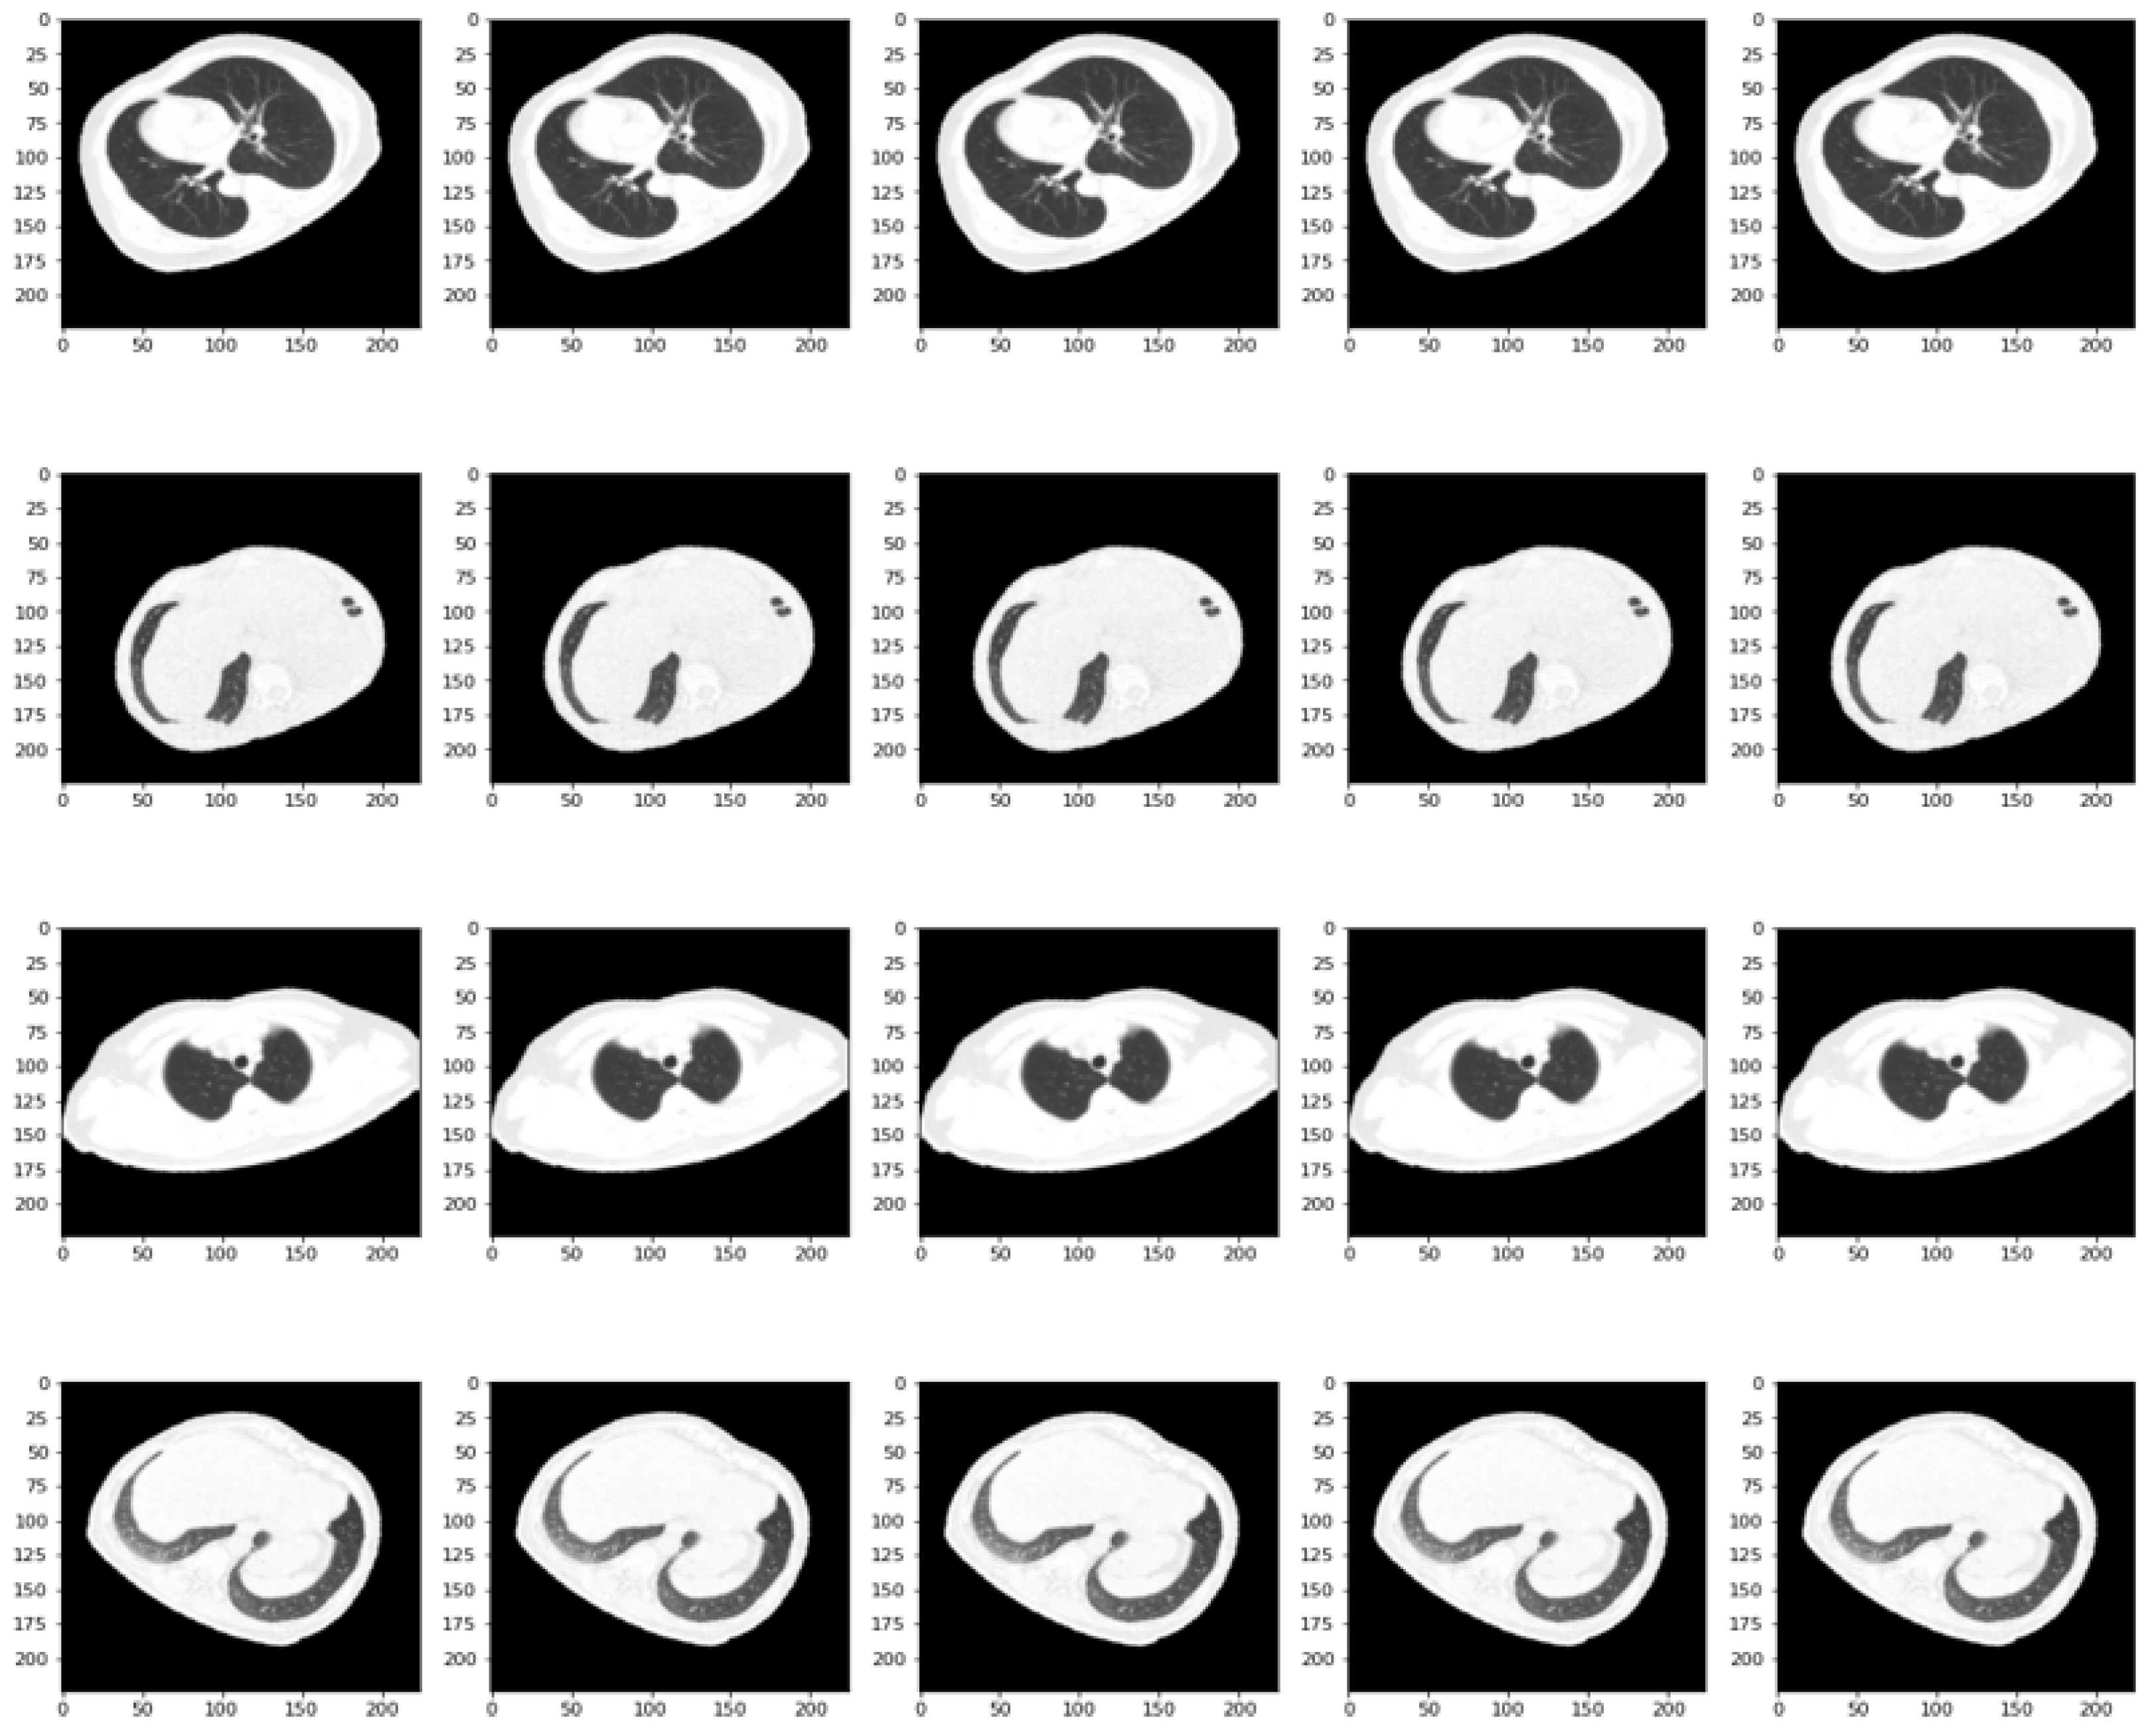

Given the limited number of tomographies, a number given using the medical approach of not constantly exposing patients to such radiation, a technique can be used to increase the size and variability of the samples, namely data augmentation. The purpose of augmentation is to make the model more robust and better generalized by exposing it to more variations and scenarios that it may encounter in real situations. By way of explanation, the object of interest in the image, in this case, the lung cavity, can be placed in different positions so that the algorithm can understand, to some extent, the meaning of the image, as can be seen in Figure 2. In this way, the pixels in the image undergo different changes via specific operations, such as rotation at different angles, translation on the horizontal and vertical axes, shifting, shear range, zoom, and horizontal flip. This approach used an instance of the “ImageDataGenerator” class from the Keras library, which can be used to perform data augmentation on images while training a neural network model. Thus, the scaling factor was assigned a value of 1/255, so that each pixel is divided by 255 to obtain values in the real range [0, 1], a process also called normalization. For the rest of the augmentation parameters, depending on the dataset, several values were tested so as not to degrade the integrity of the data.

Figure 2.

A batch of 20 samples from the resized and augmented SARS-CoV-2 Ct Scan Dataset.

After removing the noise and smoothing the image, the next step is to integrate a threshold value on the images to obtain a binary one. The optimal separation threshold between background pixels and object pixels was obtained by using the Otsu algorithm [31] such that the wavelength is determined automatically. By using this method, the need to set the threshold manually is eliminated. Next, the contours in the binary image are identified. In this way, all the contours are returned in the binary image and the hierarchy between them. Since only the largest contour represents the lung cavities, it is selected by comparing all contours according to their area. To obtain an image showing only the lung cavities, an initially empty mask is created and the largest contour is drawn on this. This will fill the inner area of the outline with white pixels and the rest of the mask will remain black. Finally, a mask is applied to the original image, which will give an image where all pixels outside the lung cavities are black. A result of such an operation at the level of available data is visible in Figure 4. The sequence of steps for preparing this data involves two main operations: extraction and augmentation. The data are extracted and then augmentation takes place.

Figure 4.

A batch of 20 samples from the resized and augmented COVID-19-CT dataset.